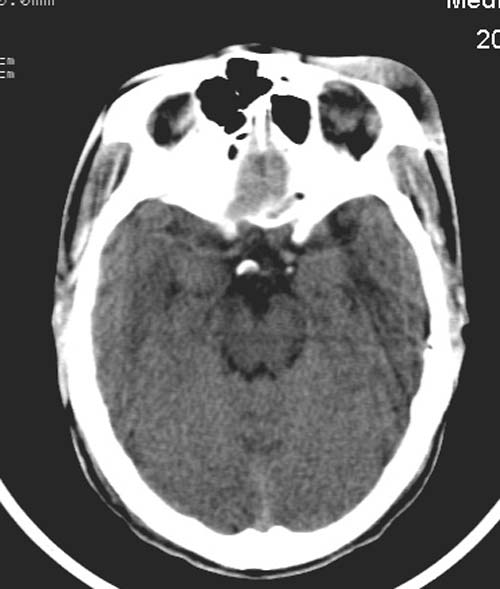

患者,男,26岁。头面部外伤半小时。

左额部软组织损伤,左泪囊损伤

既然是外伤为何无骨窗

复查一下吧,左侧颞叶两个层面都有异常密度灶。不知道是伪影不。

左侧眶部软组织肿胀,楼主是不是考虑有静脉窦血栓?复查或增强扫描。

左额部软组织肿胀,请发骨窗